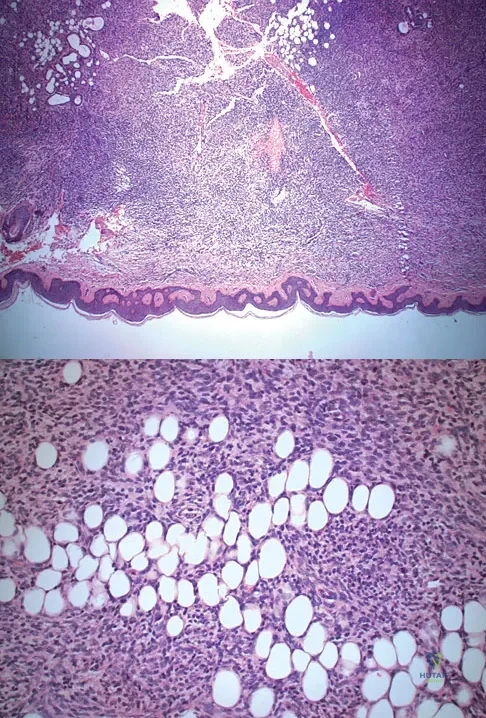

A 43-year-old woman is referred after excisional biopsy of a cutaneous soft-tissue mass from her left shoulder. Based on the biopsy specimens shown in Figures 44a and 44b, what is the best course of action?

Explanation